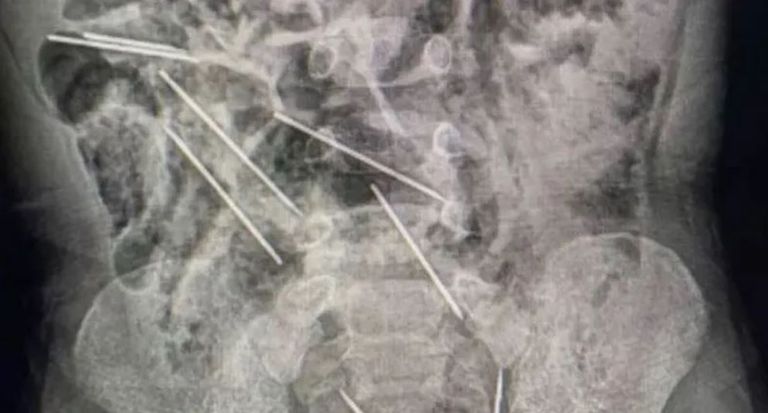

في شمال شرق بيرو، قام أطباء بإنقاذ حياة طفل يبلغ من العمر عامين بعدما ابتلع 8 إبر حقن أثناء لعبه.

أفاد الطبيب إفراين سالاسار بأنهم عندما قاموا بفتح بطن الطفل في غرفة العمليات، اكتشفوا وجود تلك القطع المعدنية وتبين أنها في الواقع إبر.

ووفقًا للتقارير الإعلامية المحلية، فإن الإبر كانت مستخدمة في تطعيم الحيوانات في مزرعة تعمل بها والدة الطفل.